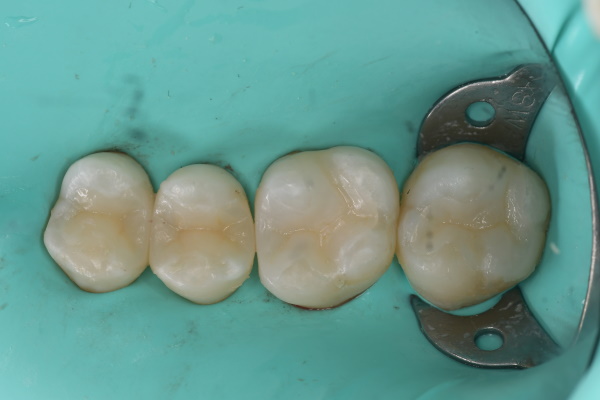

セット後

- 治療内容 セラミック治療(アンレー)

- 施術費用 88000円×4本